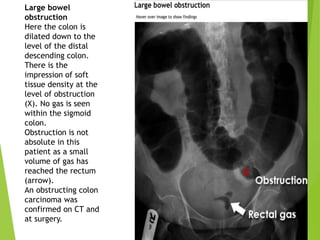

Large bowel

obstruction

Here the colon is

dilated down to the

level of the distal

descending colon.

There is the

impression of soft

tissue density at the

level of obstruction

(X). No gas is seen

within the sigmoid

colon.

Obstruction is not

absolute in this

patient as a small

volume of gas has

reached the rectum

(arrow).

An obstructing colon

carcinoma was

confirmed on CT and

at surgery.